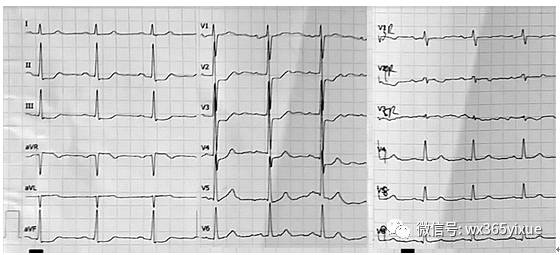

图3 患者男性,56岁。

间断性胸痛4天,加重并呈持续性胸痛2小时。既往有高血压病史10年。先登场提示V2-4导联和II、III、aVF导联ST段压低0.1mV,V8-9轻度ST段抬高(0.02mV)。入院后肌钙蛋白(cTnI)肌红蛋白均明显升高。冠脉造影显示左回旋支中段完全闭塞(箭头指示),随后开通闭塞病变并植入支架。